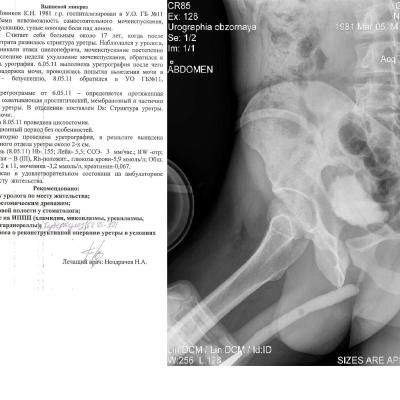

Здравствуйте! Мужу недавно сделали цистостомию, поставили диагноз: стриктура уретры (стриктура бульбозного отдела уретры около 2х см.)Стоит вопрос о "Открытой реконструктивной операции на уретре" у нас в г. Барнауле либо в Москве. Скажите пожалуйста какова вероятность успеха данной операции и как долго нужно будет находиться под наблюдением врачей, так же интересует возможно ли иное лечение при данном течении заболевания. Лечащий врач советует делать операцию в Москве, подскажите пожалуйста возможна ли бесплатная опреация, т.к. муж основной кормилец в семье, у него трое иждевенцев, я и двое детей 1 и 3 лет, наш семейный бюджет просто не потянет такую сумму. Прикрепляю фото последней уретрографии и выписку из поликлиники с точным диагнозом. Заранее большое спасибо!